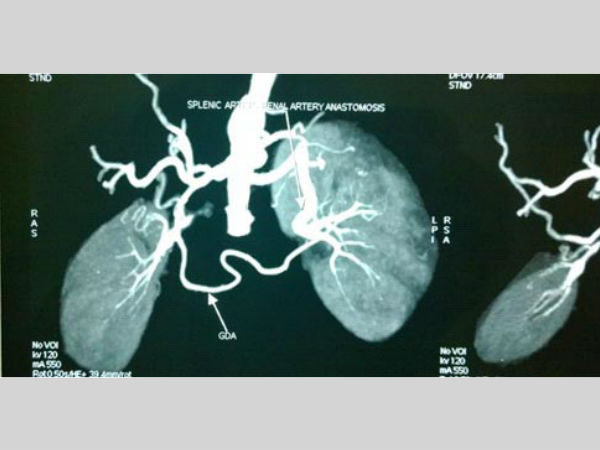

వివరాల్లోకి వెళితే సాధారణంగా ఎవరికైనా హైబీపీ అంటే 200 వరకు ఉంటుంది. కానీ, నల్గొండ జిల్లా మాచవరం గ్రామానికి చెందిన ఎ.హరికృష్ణ (19) అనే యువకుడికి అసాధారణ రీతిలో 300/120 బీపీ ఉంది. దీని వల్ల గుండె ఆర్టరీలు విపరీతంగా వాచిపోయాయి. మూత్రపిండాల్లోని రక్తనాళాలు మూసుకుపోయాయి.

దీంతో ఏడాది క్రితం అతడు ఉస్మానియా వైద్యులను సంప్రదించాడు. అతడిని పరిశీలించిన నెఫ్రాలజీ విభాగం అధిపతి డాక్టర్ మధుసూదన్.. రెండు కిడ్నీల్లోనూ గుండె నుంచి రక్తాన్ని సరఫరా చేసే రక్తనాళాలు మూసుకుపోయాయని గుర్తించారు. దాని వల్లే అనియంత్రిత బీపీ వస్తున్నట్లు నిర్ధారించారు.

రెండు దశలుగా అతడికి ఆపరేషన్ను నిర్వహించారు. తొలుత ఎడమ కిడ్నీలోని రక్తనాళాలకు బైపాస్ చేశారు. గుండె నుంచి కిడ్నీ వరకు ఎల్ ఆకారంలో కోసి శస్త్రచికిత్స నిర్వహించారు. దీంతో అతడి ఆరోగ్య పరిస్థితి అదుపులోకి వచ్చింది. ఇక, రెండో దశను మూడు రోజుల క్రితం చేసినట్లు డాక్టర్ మధుసూదన్ చెప్పారు.

ఇందులో భాగంగా కుడి కిడ్నీ రక్తనాళాలకు అదే తరహాలో బైపాస్ చేసినట్లు వివరించారు. ఈ ఆపరేషన్తో అతడి బీపీ నియంత్రణలోకి వచ్చిందని చెప్పారు. ఈ అరుదైన ఆపరేషన్ను నిర్వహించిన వైద్యులను ఆరోగ్య మంత్రి లక్ష్మారెడ్డి అభినందించారు.